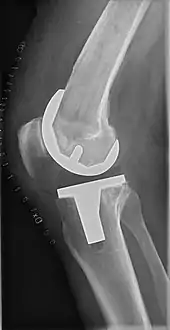

![]() |

Angles commonly measured before knee replacement surgery: |

To indicate knee replacement in case of osteoarthritis, its radiographic classification and severity of symptoms both should be substantial. Such radiography should consist of weightbearing X-rays of both knees: AP, lateral, and 30 degrees of flexion. AP and lateral views may not show joint space narrowing, but the 30-degree flexion view is most sensitive for narrowing. Full-length projections also are used in order to adjust the prosthesis to provide a neutral angle for the distal lower extremity. Two angles used for this purpose are:

- Hip-knee-shaft angle (HKS),[10] an angle formed between a line through the longitudinal axis of the femoral shaft and its mechanical axis, which is a line from the center of the femoral head to the intercondylar notch of the distal femur.[12]

- Hip-knee-ankle angle (HKA),[11] which is an angle between the femoral mechanical axis and the center of the ankle joint.[12] It is normally between 1.0° and 1.5° of varus in adults.[13]